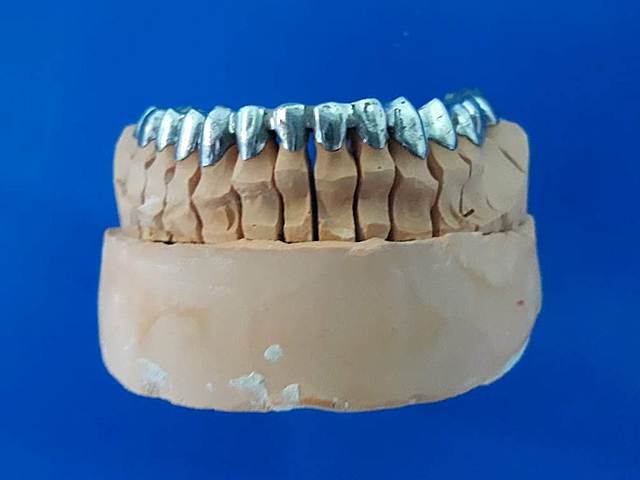

• Prueba de metal.

Prueba de metal.

Prueba de metal de prótesis fija.